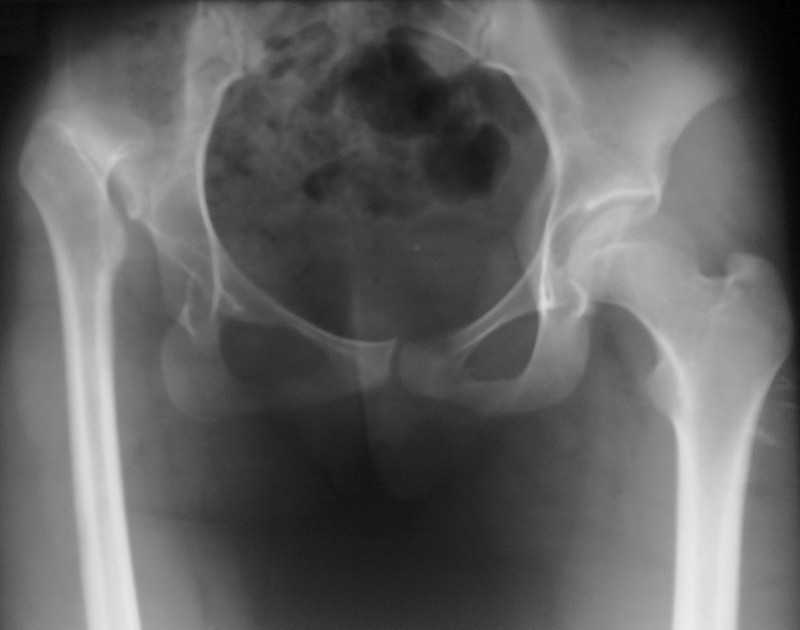

Девушка, 18 лет.Жалобы на хромоту, умеренную боль в области правого тазобедренного

сустава, укорочение левой нижней конечности, неудобства при ходьбе.Анамнез заболевания:

болеет с детства, не лечилась.Локальный статус: При стоянии на двух ногах отмечается

перекос таза вправо и деформация контура таза и в/3 бедра справа. Надколенники при перекосе

таза находятся практически на одном уровне. Отмечается S-образный сколиоз в области

поясницы справа при стоянии на двух ногах. При стоянии на левой нижней конечности сколиоз

исчезает. При стоянии на правой нижней конечности резко выражен симптом Тренделенбурга.

Визуально вальгусно-наружно-ротационная деформация правой нижней конечности,

небольшая варусная деформация (компенсаторная) левой нижней конечности. Относительная

длина правой нижней конечности 75 см, левой нижней конечности 81 см. Анатомическая длина

правого бедра 42 см, левого бедра 42 см; анатомическая длина правой голени 36 см, левой голени

35,5 см. Движения в правом тазобедренном суставе: сгибание до 70 ╨ , разгибание - 10 ╨ ,

отведение от исходного 10-15 ╨ . Ротационно: резко ограничена наружная ротация, внутренняя

ротация 10 ╨ . Длина ног от пупка справа 82 см, слева 88,5 см. Функциональное укорочение правой

нижней конечности ≈ 10 см. Движения и чувствительность пальцев левой стопы не

нарушены.Диагноз: Высокий врожденный вывих правого бедра с фронтальной нестабильностью,

выраженной вальгусно-наружно-ротационной деформацией правой нижней конечности,

функциональным укорочением правой нижней конечности до 10 см, нарушением статики и

динамики ходьбы.Вопрос - тактика лечения?Заранее благодарим!